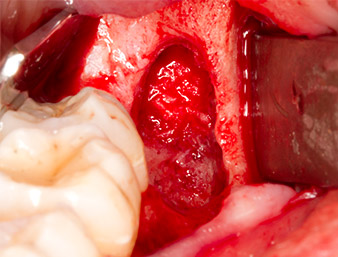

El tejido situado por encima del resto radicular no se había osificado por completo y constaba en su mayor parte de un tejido granulado con alteraciones inflamatorias (figura 4).

Con el fin de obtener material autógeno para el tratamiento posterior de la herida, se utilizó un inserto piezoquirúrgico (Piezomed B5) para obtener virutas de hueso sano del entorno del resto radicular (figura 5).